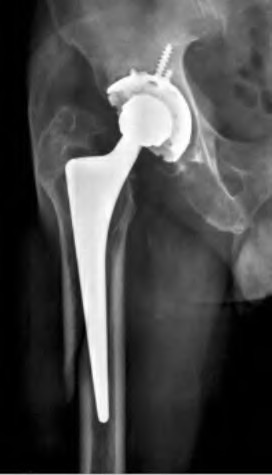

A 72-year-old female falls and sustains a periprosthetic femur fracture around her cementless total hip arthroplasty. Radiographs reveal a fracture extending just distal to the tip of the stem. The stem is radiographically loose, but there is excellent proximal and distal bone stock. According to the Vancouver classification, what is the fracture type and the recommended surgical treatment?

A 75-year-old female sustains a fall 5 years after a cementless THA. Radiographs show a periprosthetic femur fracture occurring around the stem tip. Intraoperative assessment reveals the stem remains firmly fixed in the metaphysis, and the proximal bone stock is adequate. According to the Vancouver classification, what is the fracture type and the standard recommended treatment?

A 72-year-old female presents with acute thigh pain and an inability to bear weight after a minor fall, 10 years post-THA. Radiographs demonstrate a fracture around the tip of the well-fixed femoral stem, extending into the diaphysis. The bone stock proximally remains intact. Which principle must be strictly adhered to during the surgical fixation of this fracture?